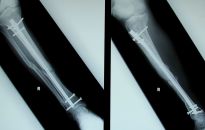

Czy wiesz, jakie urazy najczęściej grożą narciarzom i snowboardzistom?

Narciarstwo i snowboarding jest jedną z najbardziej popularnych rozrywek zimowych ? szacuje się, że obecnie na świecie jest około 200 milionów narciarzy i 70 milionów snowboardzistów. Przez wiele lat uznawane za sport elitarny, teraz stało się dostępne dla wszystkich dzięki budowie wielu...